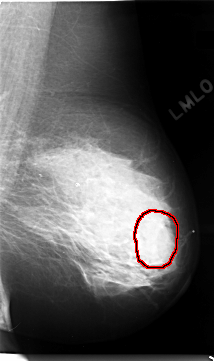

C_0017_1.LEFT_MLO

LEFT_MLO LINES 4688 PIXELS_PER_LINE 2776 BITS_PER_PIXEL 12 RESOLUTION 50 OVERLAY

FILE: C_0017_1.LEFT_MLO.OVERLAY

TOTAL_ABNORMALITIES 1

ABNORMALITY 1

LESION_TYPE MASS SHAPE LOBULATED MARGINS ILL_DEFINED

ASSESSMENT 4

SUBTLETY 1

PATHOLOGY MALIGNANT

TOTAL_OUTLINES 1

BOUNDARY